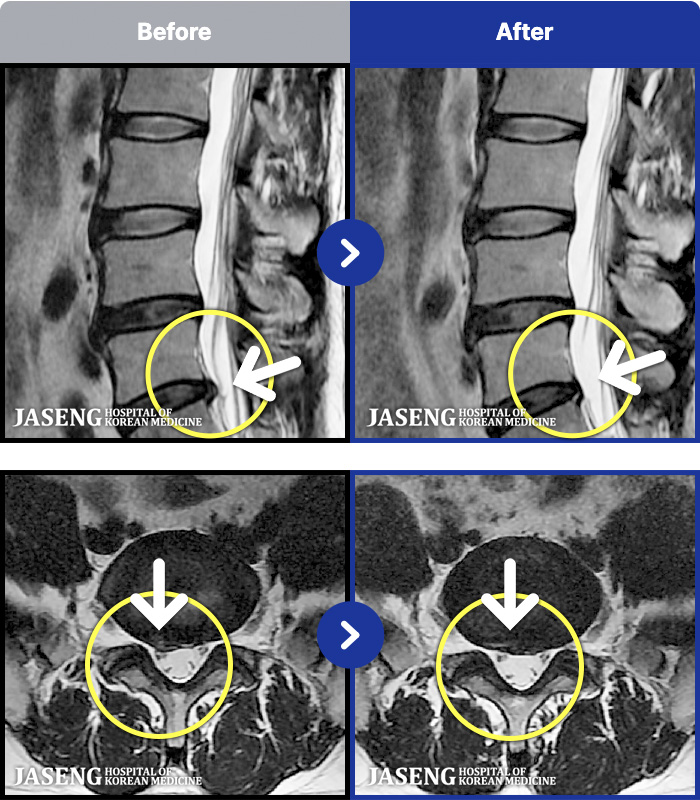

MRI ġ

1,237 MRI ũ ʸ Ȯϼ.